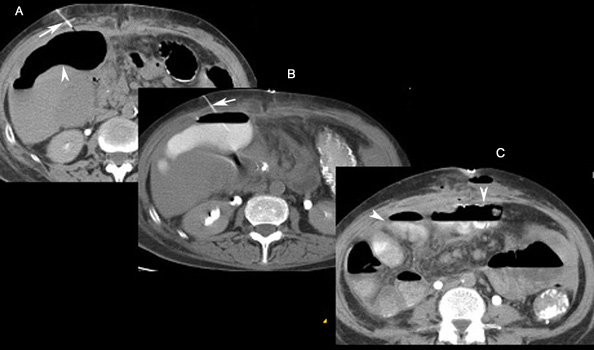

Abdominal abscess percutaneous drainage

A: Arrowheads points to a large air pocket, abscess.

B: Arrow points to a catheter. The abscess is filled with contrast.

C: Arrowheads point to small bowel loops with contrast indicating a fistulous connection between the abscess and the small bowel.